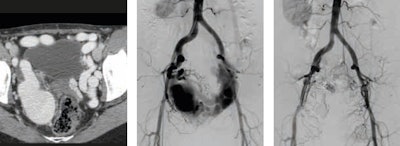

Rare findings, such as arteriovenous malformations, are extremely challenging and require accurate diagnosis and appropriate treatment, especially if they are high-flow and/or extensive lesions. Embolization with coils and 98% ethanol is just one of the many existing treatment possibilities (see figure 3).